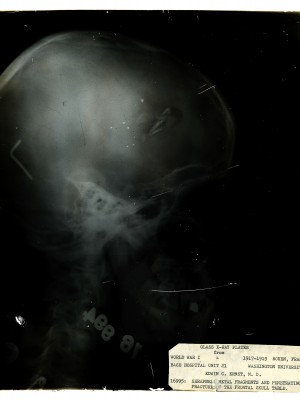

Dr. Edwin Ernst, an only child born to St. Louis residents Charles and Catherine Ernst, was a notable Roentgenologist, a physician who specializes in radiological work. Dr. Ernst studied at Washington University in St. Louis and later at Moravian College in Bethlehem, Pennsylvania earning his advanced degrees. For two years he served as a resident physician at the St. Louis Mullanphy Hospital before leaving to pursue a private practice. When the United States formally entered the war in 1917, Ernst left St. Louis to become chief radiologist at Base Hospital 21. He was discharged honorably in 1919 with the citation of Major. His collection consist of x-ray images taken at Base Hospital 21 as well as drawings of radiological equipment and photographs.